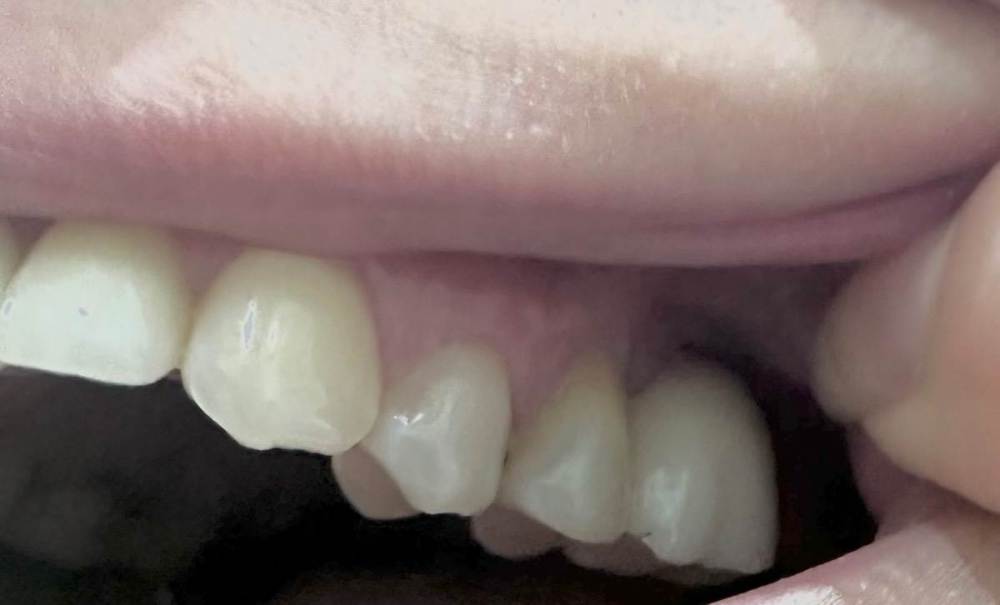

Mitt Опубликовано 29 октября, 2023 Поделиться Опубликовано 29 октября, 2023 (изменено) Здравствуйте. Ж., 39 лет. Так получилось, что мне нужно решить, что делать с имплантатом на месте верхней шестерки. А тк я не обладаю необходимой компетенцией, очень нуждаюсь в подсказках специалистов. Дано: 1. 2014-2015 гг - удаление зуба, синус лифтинг, имплантация с пластикой мягких тканей, установка коронки. 2. 2015 - 2019 гг - проблема контактов с рядом находящимися пятым и седьмым зубами, воспаление десны вокруг 5, имплантант, 7. Решалось путем композитных «накладок» на 5 и 7 зубы. 3. 2019 - 2023 гг - пластика мягких тканей, удаление 7 зуба с подсыпкой графта, еще штуки 3 или 4 пластики, включая вестибулопластику, временная коронка. 4. 2023 г - установка новой постоянной коронки, 5 месяцев тишины, с августа гной в районе имплантата (десна спокойна). Проблемы общие для всех временных периодов - тандем с пазухой и периодические ближе к постоянным боли разной интенсивности и локации (пазуха, 7 зуб, место от 7 зуба, стенка носа, кость), мне сложно лоцировать( Мне нужно выбрать, что делать дальше: попробовать почистить имплантат, или уже отпустить=удалить. Вариант почистить и еще сделать пластику пока не рассматриваю, тк после стольких пластик частичная парастезия неба. Может быть, кто-то подскажет, к какому решению в итоге прийти.. P.s. Я не знаю , какие скрины кт нужны( кт 08.2023 Изменено 29 октября, 2023 пользователем Mitt Ссылка на комментарий